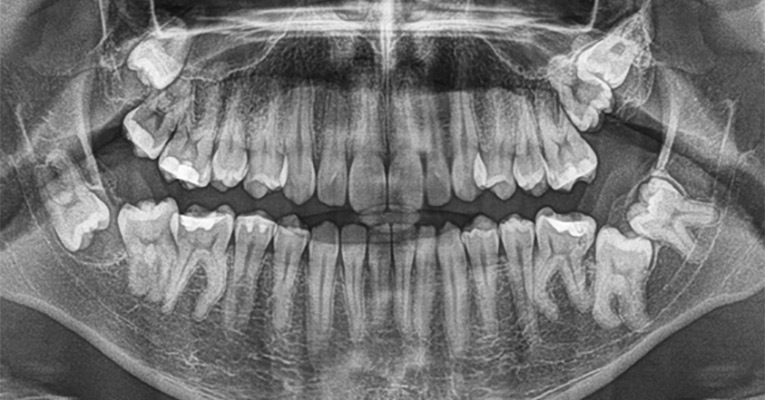

RTG panoramiczne zębów to inaczej zdjęcie pantomograficzne. Pozwala ono na dokładne obejrzenie wszystkich zębów, stawów skroniowo żuchwowych, zatok szczękowych, ale też kości szczęki i żuchwy. Stosuje się je nie tylko w stomatologii, ale też chirurgii szczękowo-twarzowej, w leczeniu implantologicznym, protetycznym, w periodontologii i w ortodoncji.

Urządzenie wykonujące takie zdjęcie RTG zęba to pantomogram, który podczas pracy obraca się wokół głowy Pacjenta.

Zdjęcie pantomograficzne wykonuje się na stojąco. W ustach Pacjenta umieszczony zostaje specjalny uchwyt stabilizujący głowę. Następnie dana osoba zostaje w odpowiedni sposób ustawiona, by obraz mógł być jak najdokładniejszy. Zdjęcia pantomograficzne zębów pozwalają właściwie zaplanować leczenie i zdiagnozować wiele różnych dolegliwości jednocześnie.